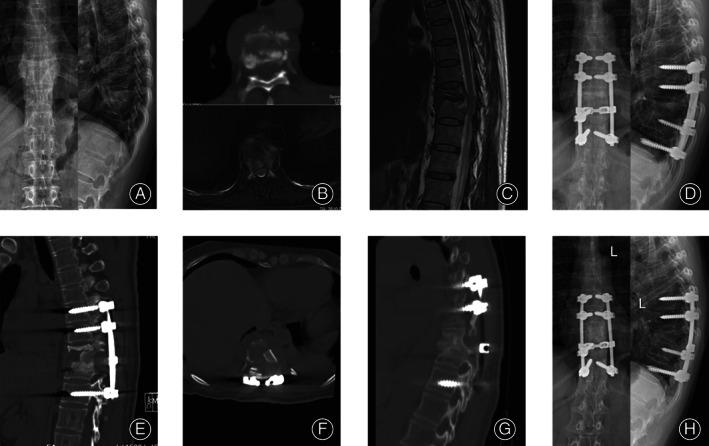

Mid-thoracic spinal tuberculosis is prone to kyphotic deformities and neurologic impairment. Posterior approach can effectively restore the spinal stability by reconstructing the anterior and middle spinal columns. Titanium mesh cages (TMC), allogeneic bone (ALB), and autogenous bone (AUB) are three main bone graft struts. We aimed to compare the therapeutic efficacy of three bone graft struts, for anterior and middle column reconstruction through a posterior approach in cases of mid-thoracic spinal tuberculosis.

The follow-up duration was at least 3 years. All patients achieved a complete cure for spinal TB. Neurological performance and quality of life were remarkably improved at the final follow-up. The intraoperative blood loss, operation time and VAS values 1 day postoperatively for TMC group and ALB group were significantly lower than those in AUB group (P < 0.05). The duration of bone graft fusion in ALB group (18.1 ± 3.7 months) was longer than that in TMC group and AUB group (9.5 ± 2.8 and 9.2 ± 1.9 months) (P < 0.05). No significant intergroup differences were observed in terms of age or preoperative, 3-months postoperative, and final follow-up indices of ESR and CRP among the three groups (P > 0.05). At the final follow-up, the correction loss was mild (2.1 ± 0.9, 2.2 ± 1.0, 2.1 ± 0.8) and Cobb's angles of the three groups were 20.1 ± 2.9, 20.5 ± 3.2, 20.9 ± 3.4, respectively, which were remarkably rectified in comparison with the preoperative measurements (P < 0.05).

In terms of postoperative recovery and successful fusion rate of bone graft, it seems that posterior instrumentation, debridement, and interbody fusion with titanium mesh cages are more effective and appropriate surgical methods for mid-thoracic spinal tuberculosis.